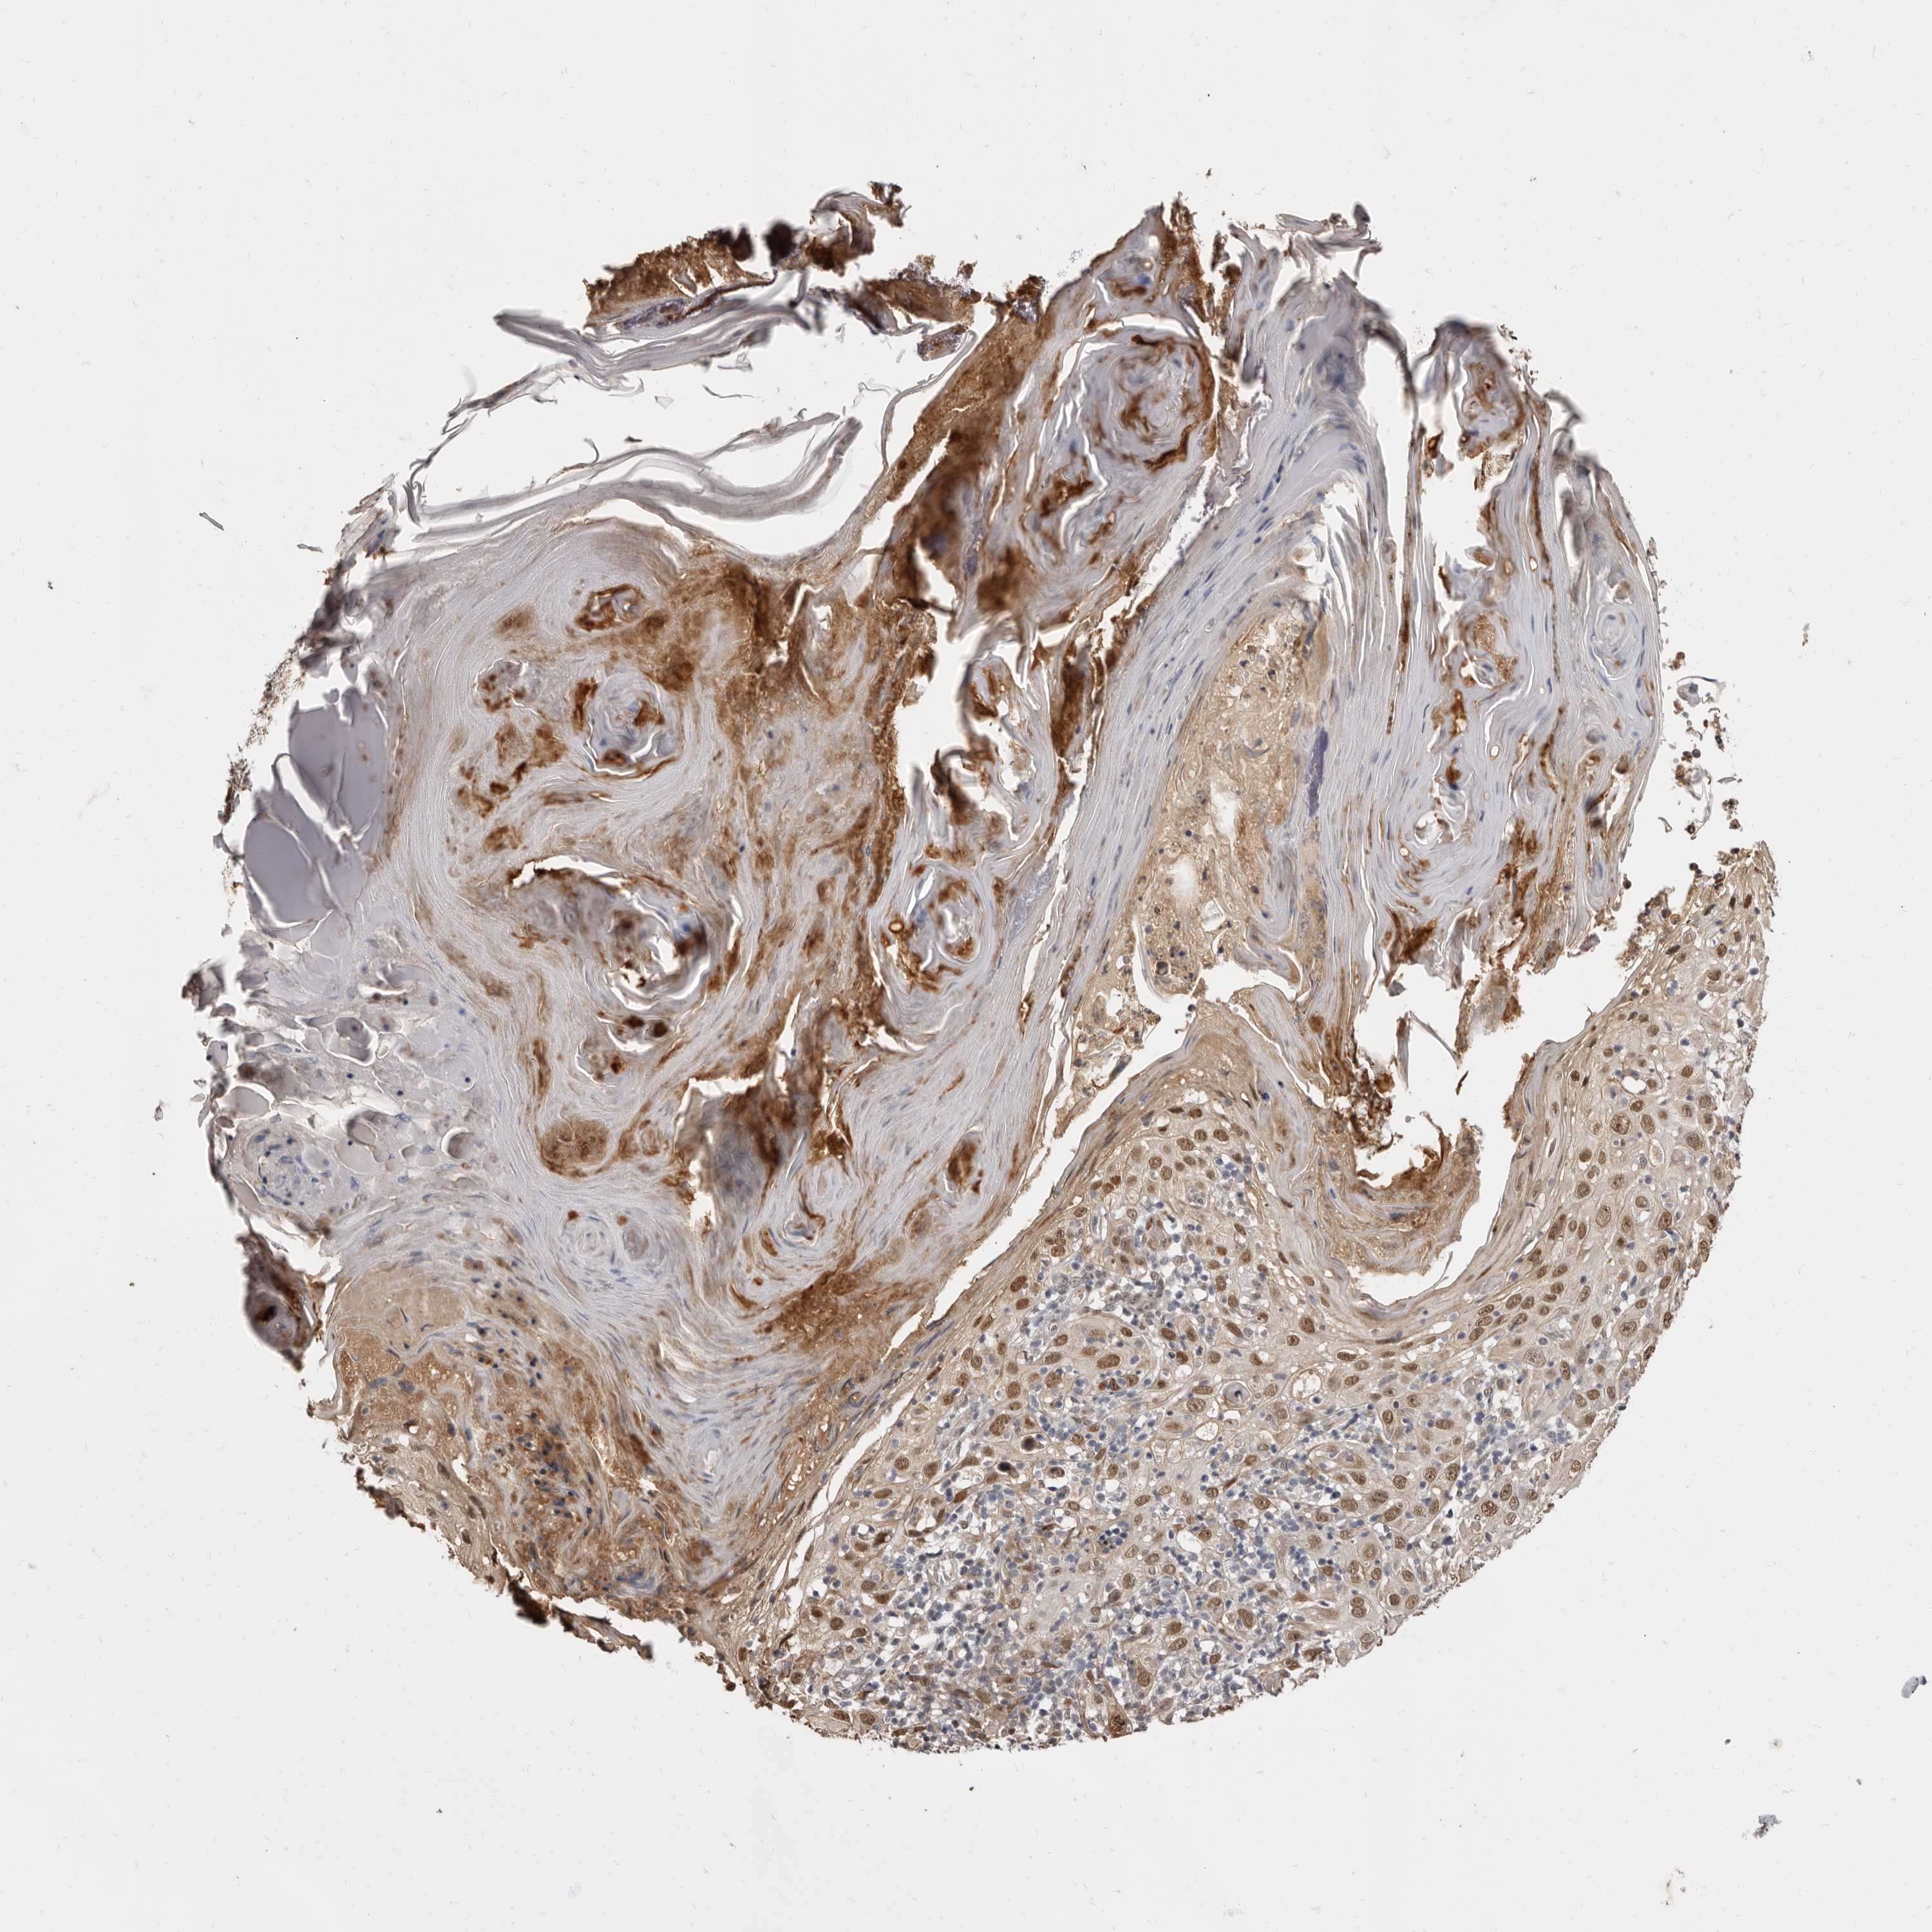

SKIN CANCER - Protein expressioni

A mouse-over function shows sample information and annotation data. Click on an image to view it in a full screen mode. Samples can be filtered based on level of antibody staining by selecting one or several of the following categories: high, medium, low and not detected. The assay and annotation is described here.

Antibody staining in the annotated cell types in the current human tissue is reported as not detected, low, medium, or high, based on conventional immunohistochemistry profiling in selected tissues. This score is based on the combination of the staining intensity and fraction of stained cells.

Each image is clickable and will lead to virtual microscopy that enables deeper exploration of all samples and also displays staining intensity scores, fraction scores and subcellular localization as well as patient and tissue information for each sample.

Antibody HPA028461

Antibody HPA028466

Squamous cell carcinoma, NOS